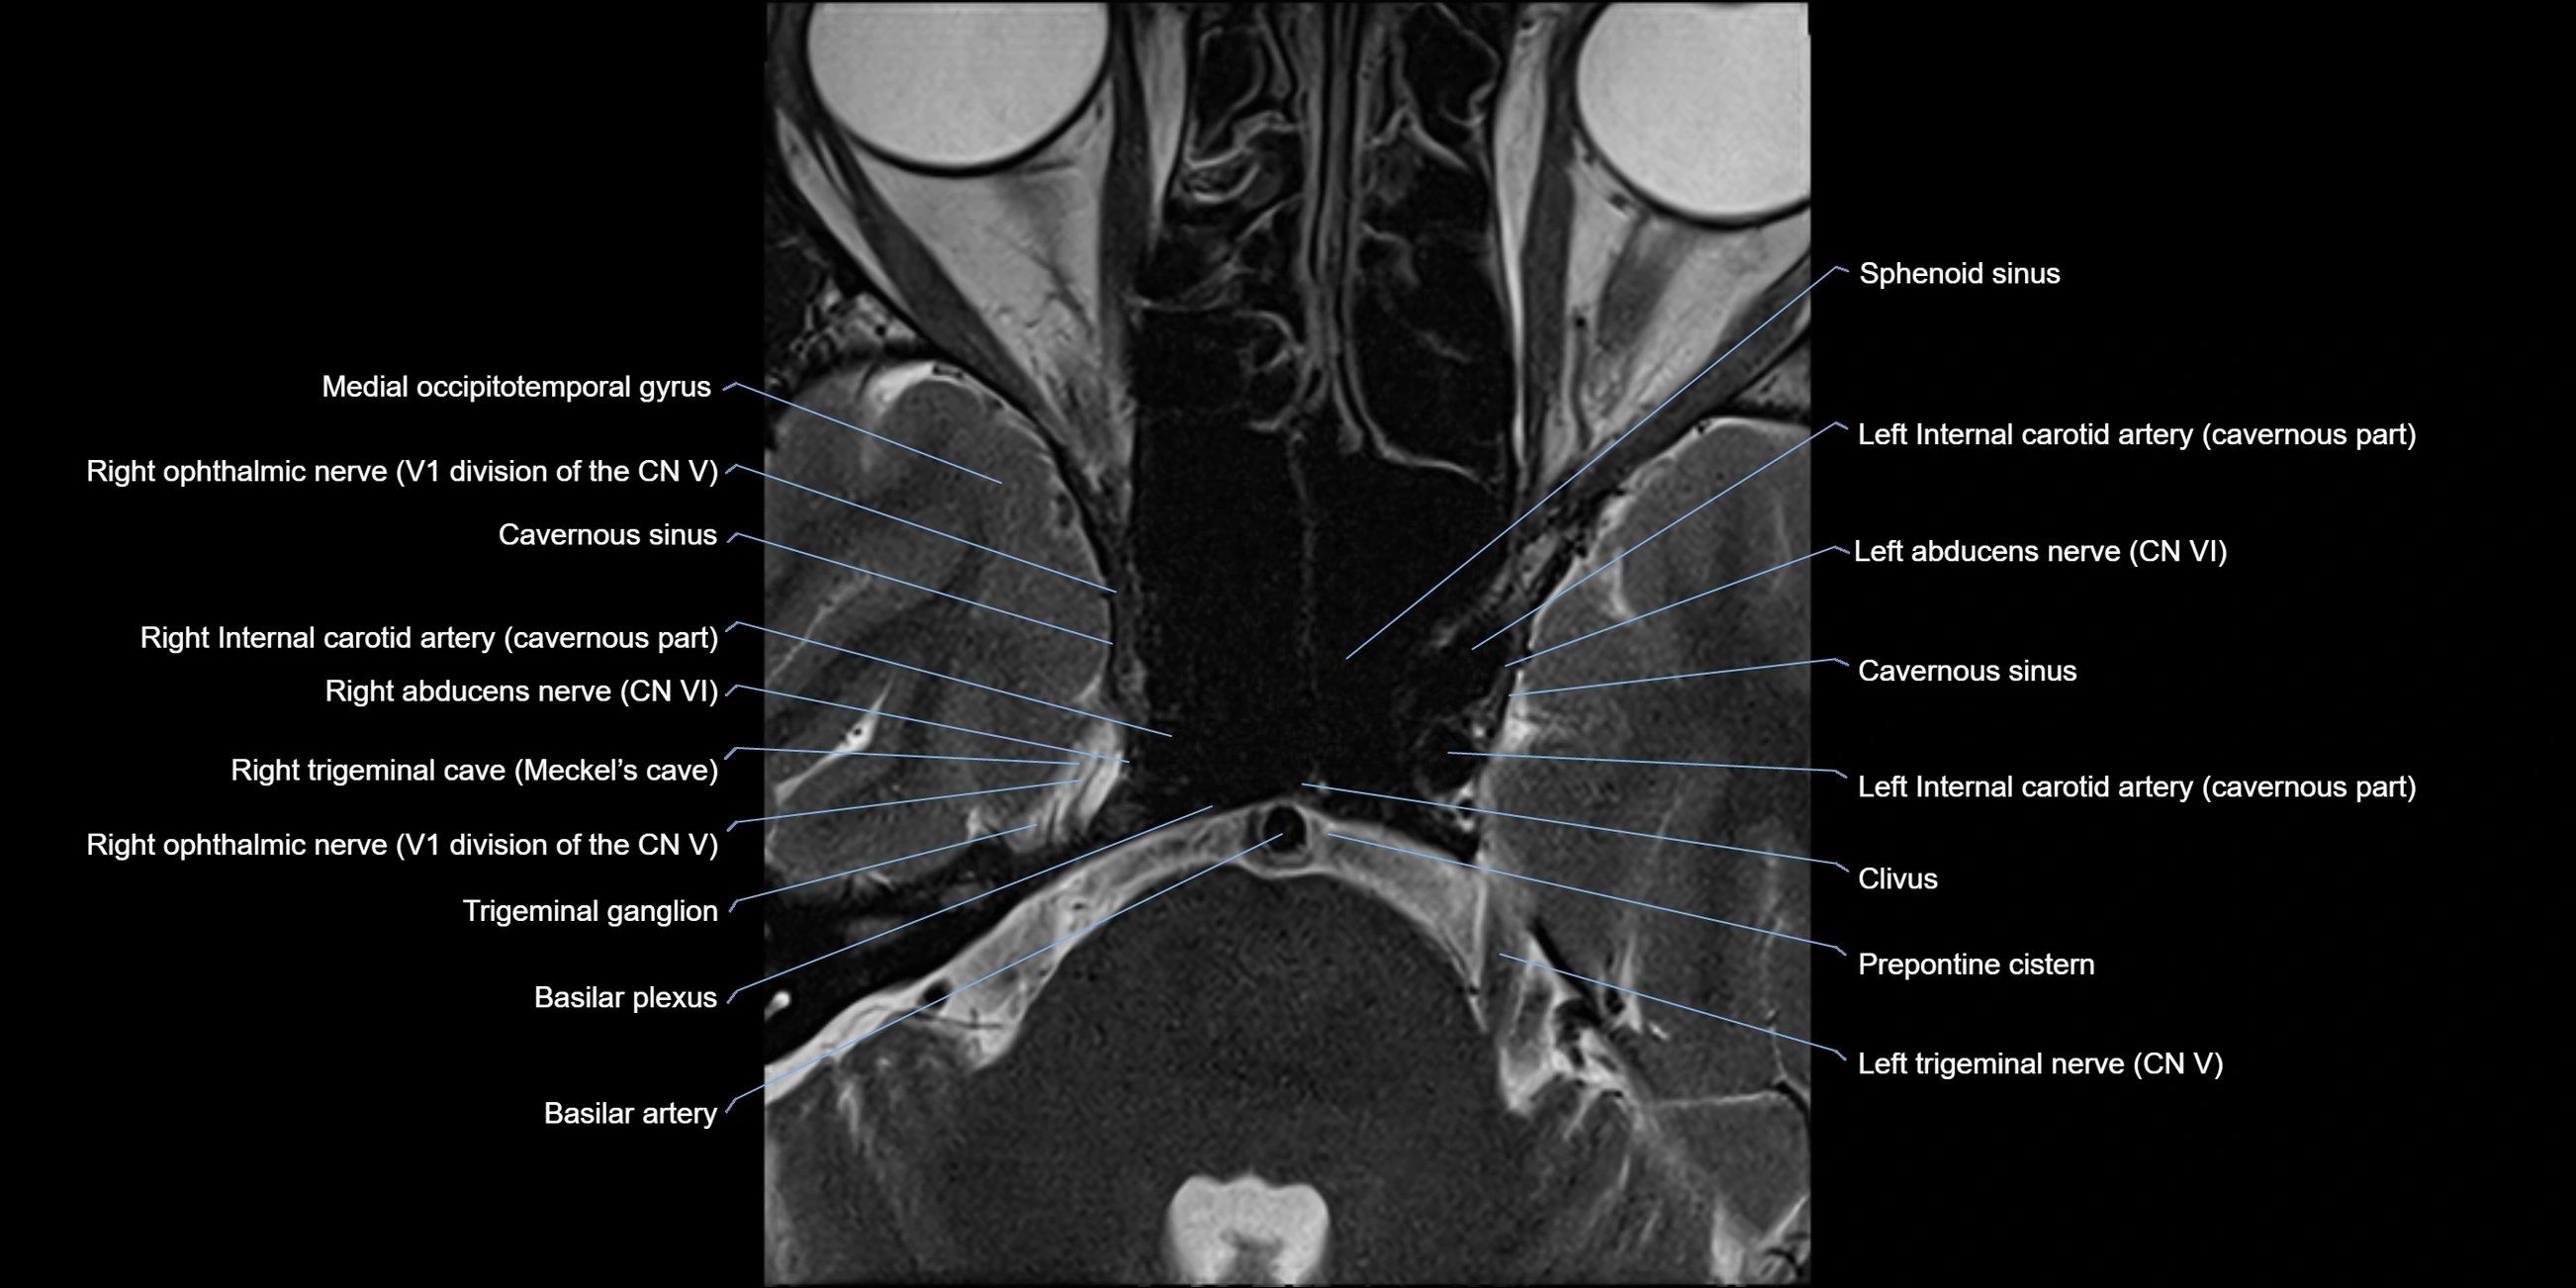

MRI Appearance

The abducens nerve is a small, thin, linear structure

Best visualized on high-resolution T2-weighted 3D MRI sequences (e.g., FIESTA or CISS)

Seen as a hypointense (dark) line running from the brainstem at the pontomedullary junction, traversing the prepontine cistern, and entering Dorello’s canal under the petrosphenoidal ligament, then into the cavernous sinus, and finally the orbit

May be challenging to visualize in standard MRI due to its small size

Pathology may be inferred by absence, displacement, or enhancement of the nerve

MRI images